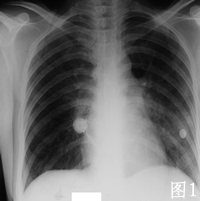

2001年7月患者无明显诱因出现间断性发热,体温最高达38℃,无伴随症状,给予青霉素等治疗可好转。2002年3月底患者再次出现发热,体温在38℃左右,伴畏寒、咳嗽、咳白痰和胸闷气短,血常规正常,先后给予多种抗生素治疗无效。4月底在我院就诊时发现人免疫缺陷病毒抗体HIV Ab初筛和确证试验均阳性,CD4+ T淋巴细胞仅14/μk,X线胸片和胸部CT显示双肺弥漫性片状浸润阴影(见图1、2)。确诊AIDSC3期,结合患者胸部影像学表现和进行性呼吸困难,考虑卡氏肺孢子虫(PCP)肺炎可能性大,于4月29日开始给予复方磺胺甲 唑(复方新诺明,SMZCO2片,每日4次。患者自发病以来,食欲明显减退,体重下降10 kg。

患者入院后在坚持SMZCO治疗的同时,为促进肺部炎症迅速吸收,短期给予大剂量泼尼松治疗泼尼松60 mg/d,每3~4日减20 mg,2周内停用,患者呼吸困难迅速缓解,血氧饱和度由90%上升到99%。2周后SMZCO减为2片/d维持治疗。2周后复查X线胸片和胸部CT(见图3、4),见双肺的阴影明显吸收,但右上肺病灶没有吸收。考虑患者合并感染肺结核,给予异烟肼、乙胺丁醇和吡嗪酰胺治疗。从5月10日开始给予患者叠氮胸苷、拉米夫定和印地那韦进行高效抗逆转录病毒治疗HAART。